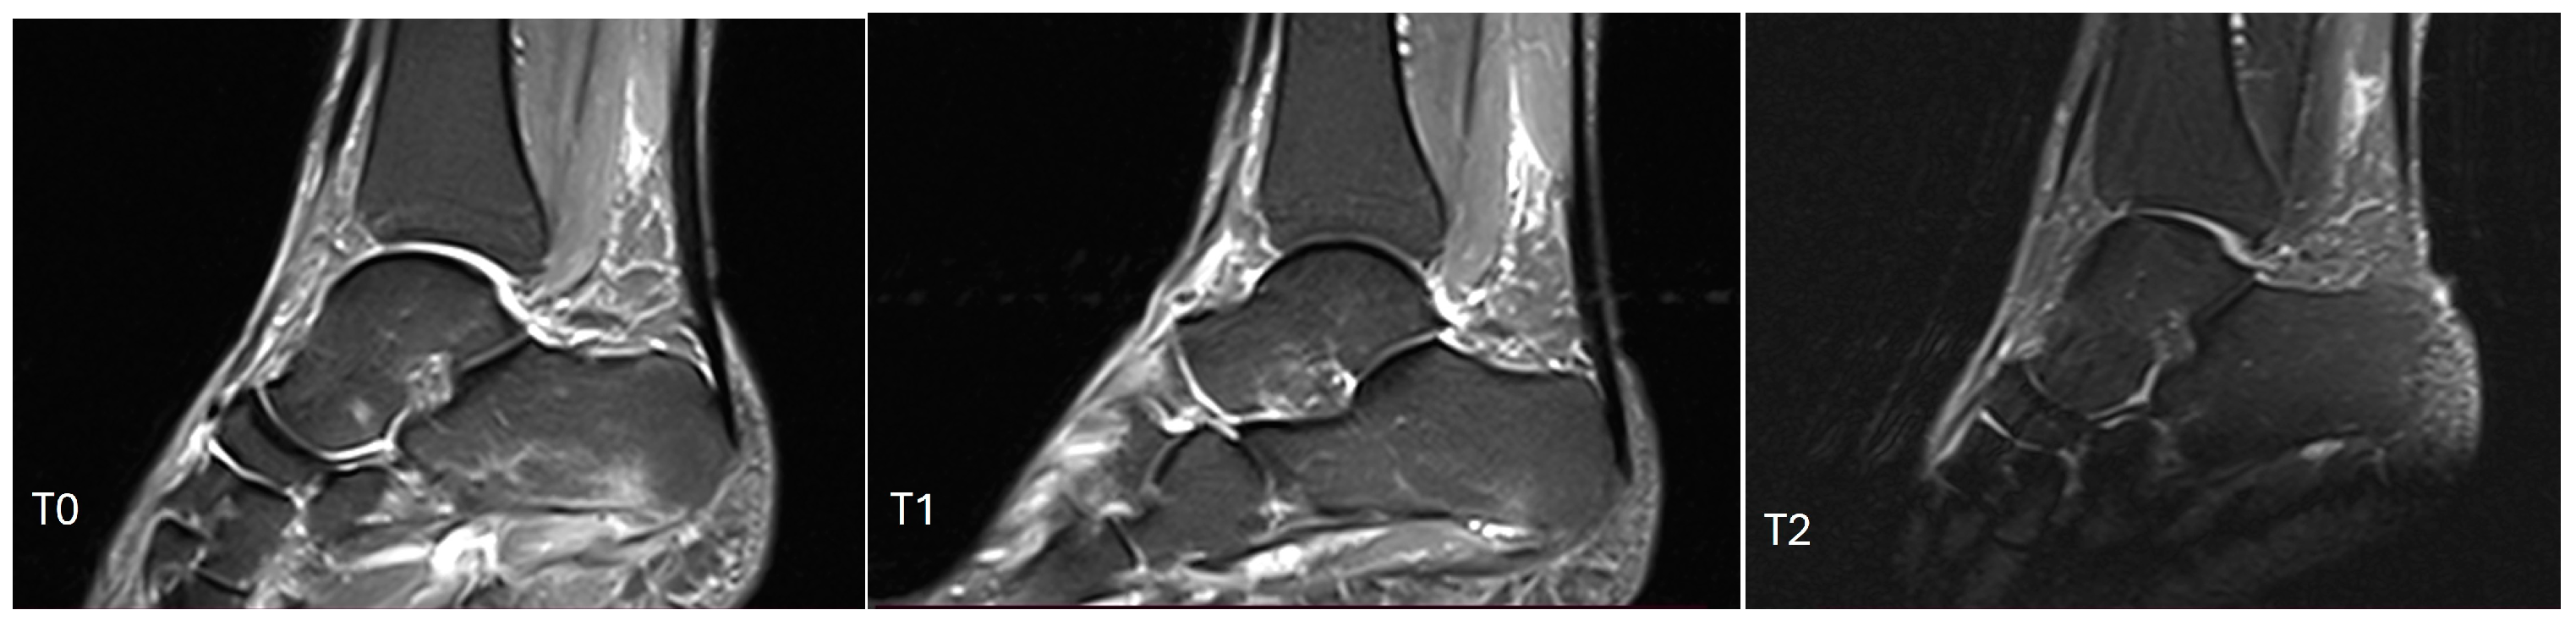

| Presence of bone edema | No | 23 | 48.94 |

| Yes | 24 | 51.06 | |